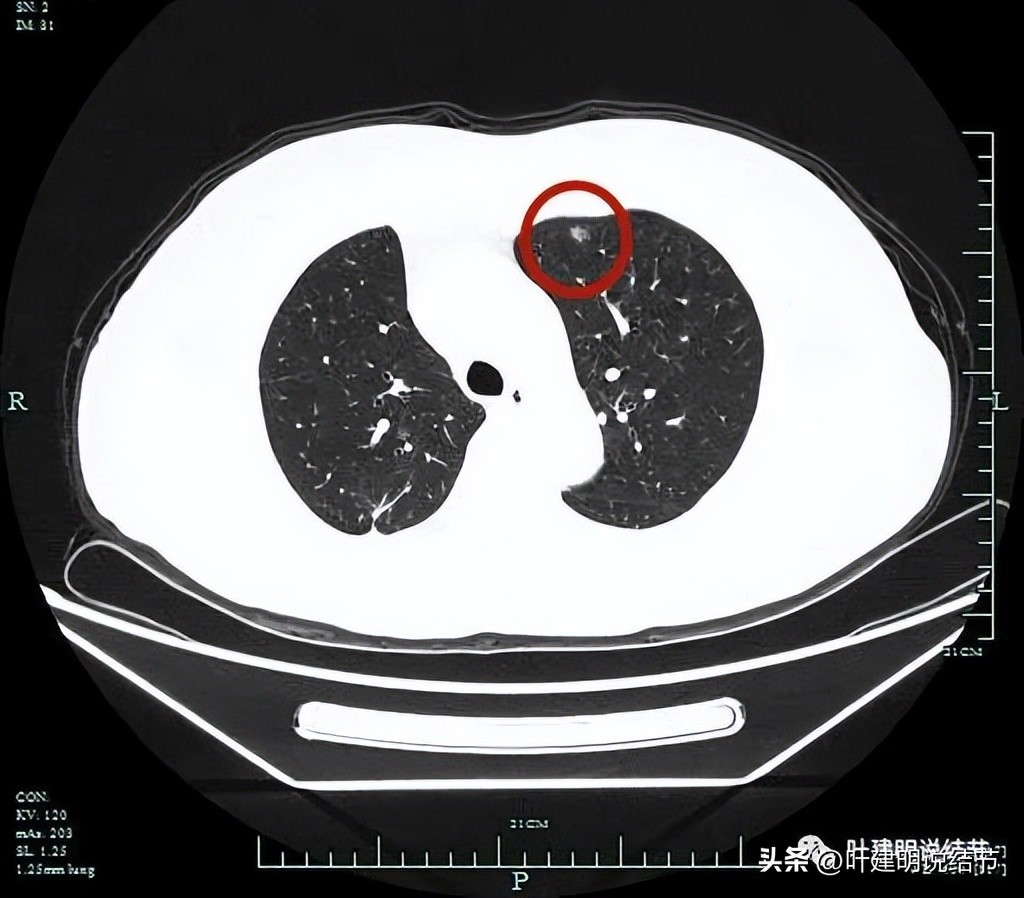

左上病灶2:胸膜下微小磨玻璃结节,也是轮廓较清的。

靶扫描显示主病灶混合磨玻璃密度,边缘实性成分(粉色箭头);瘤肺边界清(红色箭头);部分边缘似有毛刺(紫色箭头)。

灶内实性成分(粉色箭头)以及微血管进入(桔色箭头);整体密度不均,轮廓与瘤肺边界清(红色箭头)。

微血管征、毛刺征、混合磨玻璃密度、胸膜间隙征(黄色箭头)。

左肺上叶两处病灶都要考虑是恶性的,其中主病灶混合磨玻璃密度,有微血管进入与穿行;有毛刺征;有胸膜间隙征;有表面不平与内部密度不均;有偏实性成分,应该是浸润性腺癌或微浸润性腺癌可能性大,位置好,能楔形切除,建议手术干预处理。左上次病灶小,但也是肿瘤范畴的,如果没有主病灶在,可随访,但主病灶要楔形切除,则可考虑一并切除。病理可能是不典型增生或原位癌可能性大些。